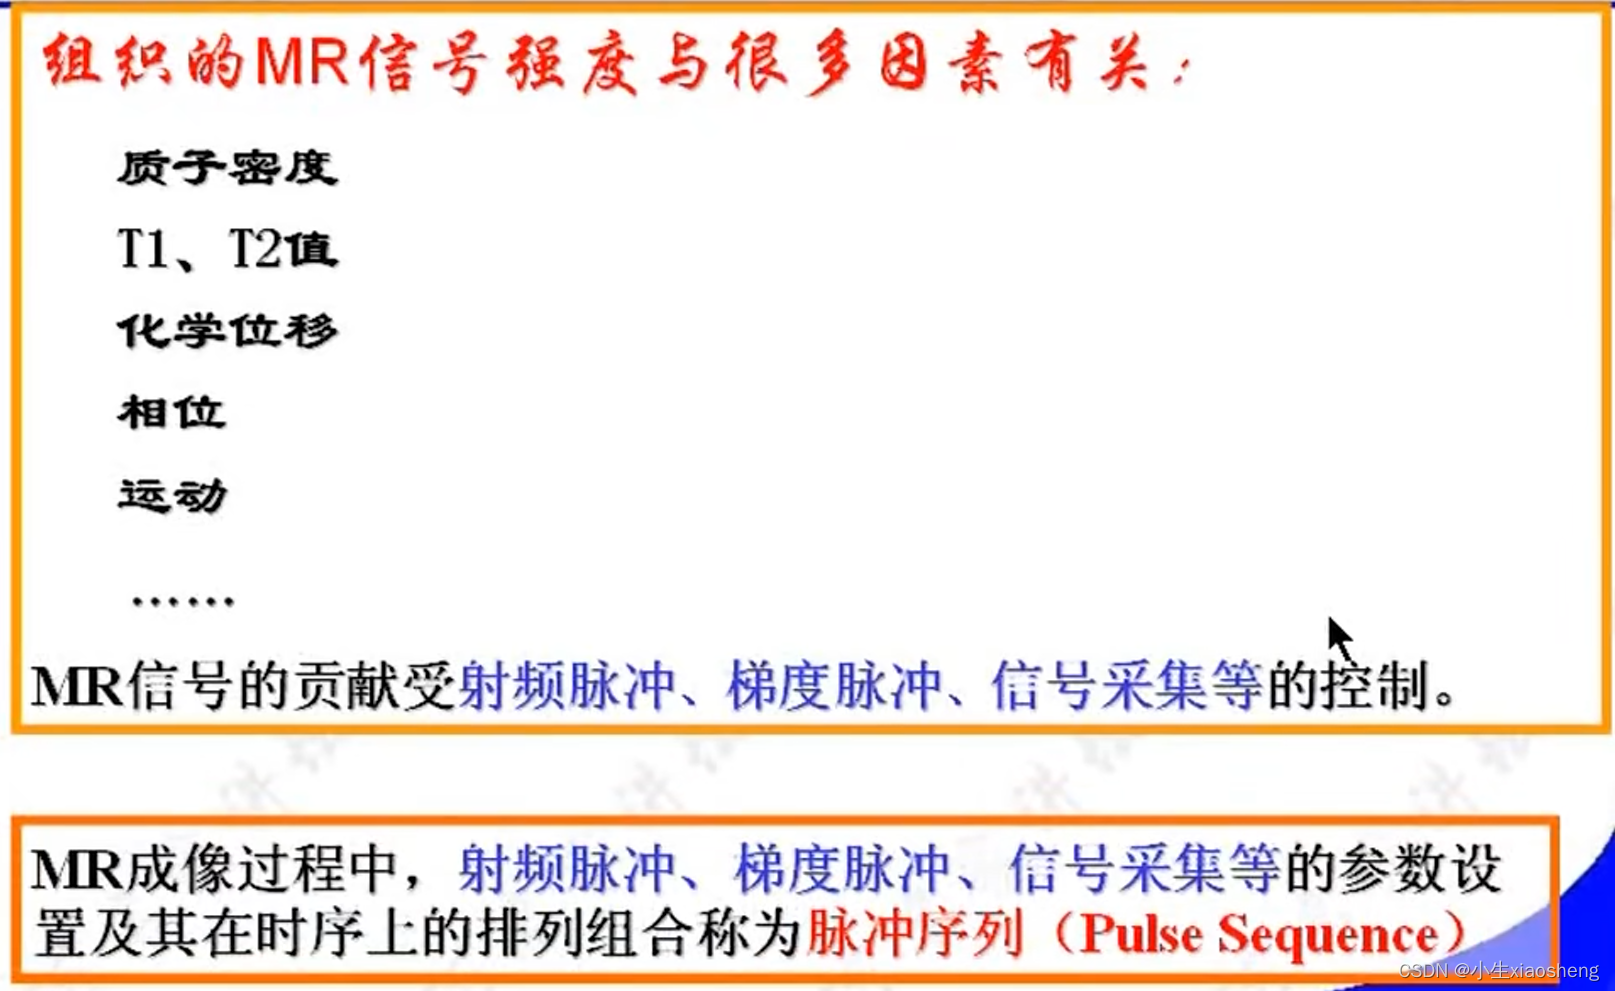

TR代表重复时间(repetition time),是指脉冲序列执行所需的时间

TE代表回波时间(echo time),是指产生宏观横向磁化矢量的脉冲中点到回波中点的时间间隔

T1(纵向弛豫时间):当射频脉冲信号解除后,激发状态的氢原子核会慢慢释放能量,同时相位和能级会恢复到开始状态、磁化矢量也会恢复到平衡状态。这个过程被称为纵向弛豫

T2(横向弛豫时间):关闭射频脉冲后,质子不再处于同步、同相位状态,指向同一方向的质子散开,导致横向磁化矢量从最大衰减到零。这个过程被称为横向弛豫。

相位编码梯度和频率编码梯度/读出梯度:主要功能就是在脉冲消失之后采集数据,能横向量编码很快衰减。